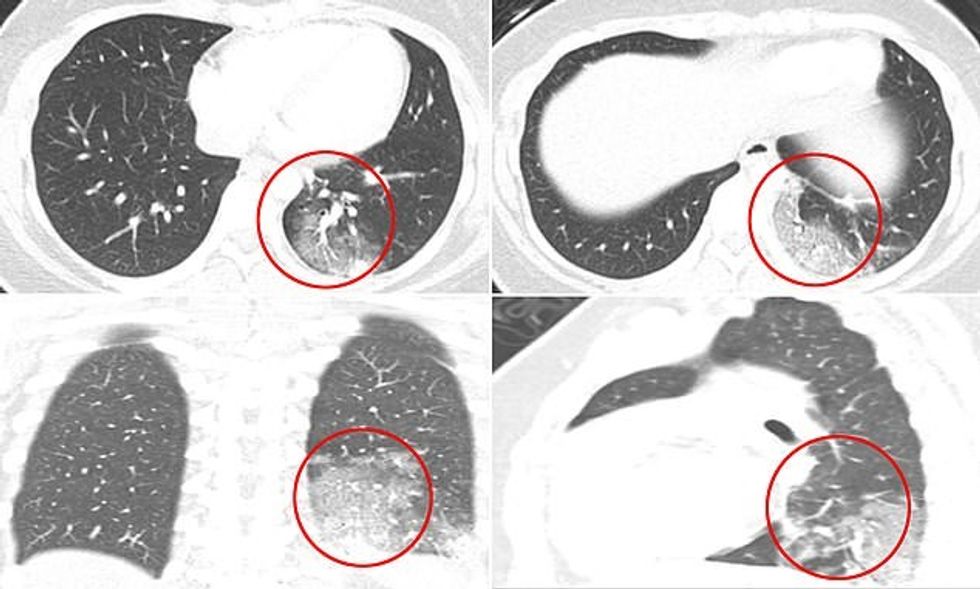

Në një studim të 20 fëmijëve, pothuajse dy të tretat kishin Ground-glass opacity (GGO) (zonë me mjegull të shtuar në mushkëri), një tregues i inflamacionit të përhapur.

Gjysma e pacientëve kishin atë që njihet si ‘shenja halo’, që ndodh kur inflamacioni rrethon një masë, e njohur si konsolidim.

Konsolidimi e bën të vështirë frymëmarrjen sepse qeskat e ajrit të mushkërive janë të mbushura me substanca të tilla si lëngu ose infeksioni.

Gjashtë në dhjetë pacientë kishin një GGO, e cila është një re e mjegullt mbi mushkëri që tregon një larmi problemesh.

Mund të nënkuptojë që mushkëritë janë të mbushura pjesërisht me lëndë jo të zakonshme, ka trashje të indeve të mushkërive ose kolaps të pjesshëm të valvuleve - qeskat e vogla ajrore të mushkërive.

Gjysma kishte konsolidim, që është hapësira ajrore në mushkëritë e tyre të mbushura me një substancë, zakonisht qelb, gjak ose ujë.

Radiografët e quajnë atë “shenjën e halo”, dhe megjithëse është një tipar i zakonshëm i sëmundjes së mushkërive, mund të jetë më unik për COVID-19.